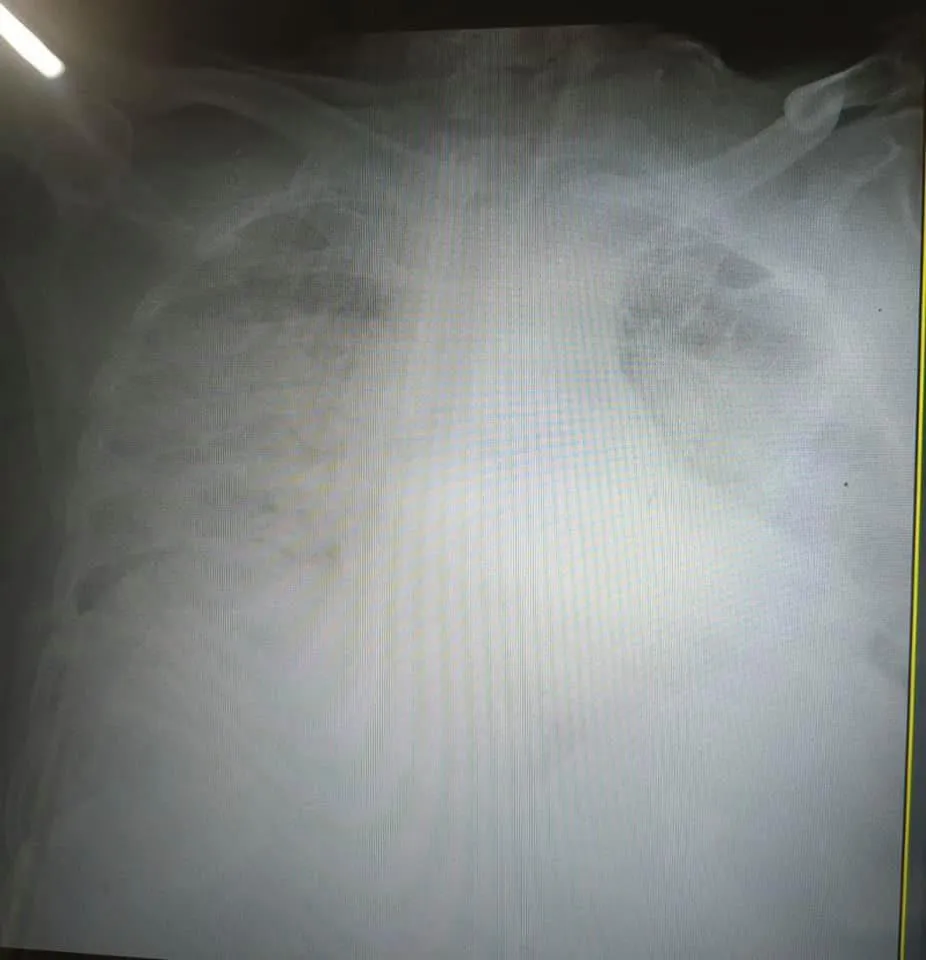

Пошкодження легенів коронавірусом / Фото Facebook Ірина Заславець

Яка ситуація з коронавірусом у Львівській області

- Львівська область перебуває на третьому місці за кількістю хворих на коронавірус в Україні після Києва та Харківської області.

- У Львівській області захворіло 42 050 людей. Від хвороби померло 1 176 осіб, одужало – 27 222.